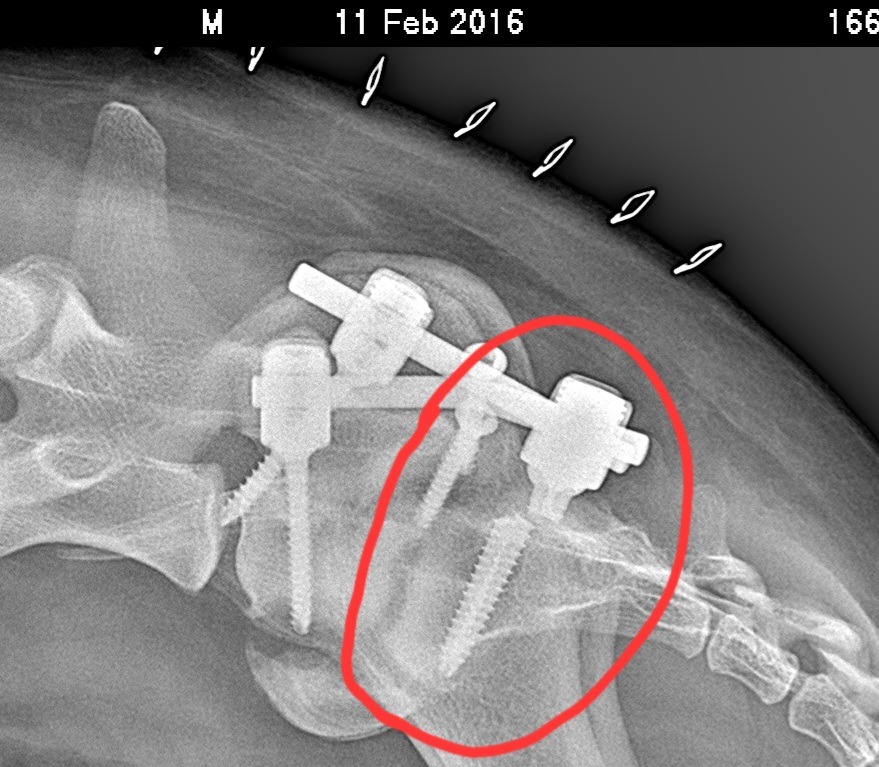

Happy ha eseguito l'operazione, ma purtroppo a distanza di 10 giorni le viti sulla vertebra S1 si sono spezzate e dovrà affrontare un ulteriore operazione.

Allego la nuova lastra con le viti spezzate